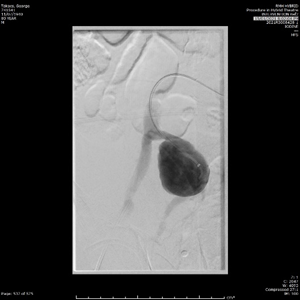

He had normal inflammatory markers, Hb 133g/L and Creatinine 104umol/L. A Computed Tomography (CT) scan of the abdomen and pelvis was performed, with the differentials considered being incarcerated inguinal hernia, diverticulitis or malignancy. However, the CT showed a 75mm, contained ruptured right internal iliac artery (IIA) aneurysm, with no active contrast extravasation (Figure 1). There was perianeurysmal haemorrhage in the right iliac fossa which extended into a small fat-containing inguinal hernia (Figure 2). There was also bladder distension and moderate-to-severe right hydroureteronephrosis secondary to the large aneurysm.

Figure 2 CT images of the abdomen and pelvis. (A) Coronal image showing perianeurysmal haemorrhage in the right iliac fossa extending into an inguinal hernia. (B) Axial image showing the right inguinal hernia containing blood, as compared to left inguinal hernia containing fat only.